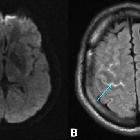

Radiographic features

Intracranial mycotic aneurysms can be evaluated with CT, MRI, or angiography .

Classically, the peripheral location of intracranial mycotic aneurysms allows them to be differentiated from berry aneurysms , however more proximal aneurysms can be impossible to differentiate from berry aneurysms on any imaging modality . Morphologically, these aneurysms are typically small , although rarely giant intracranial mycotic aneurysms have been described , and are typically fusiform (more common), saccular or sacculofusiform .